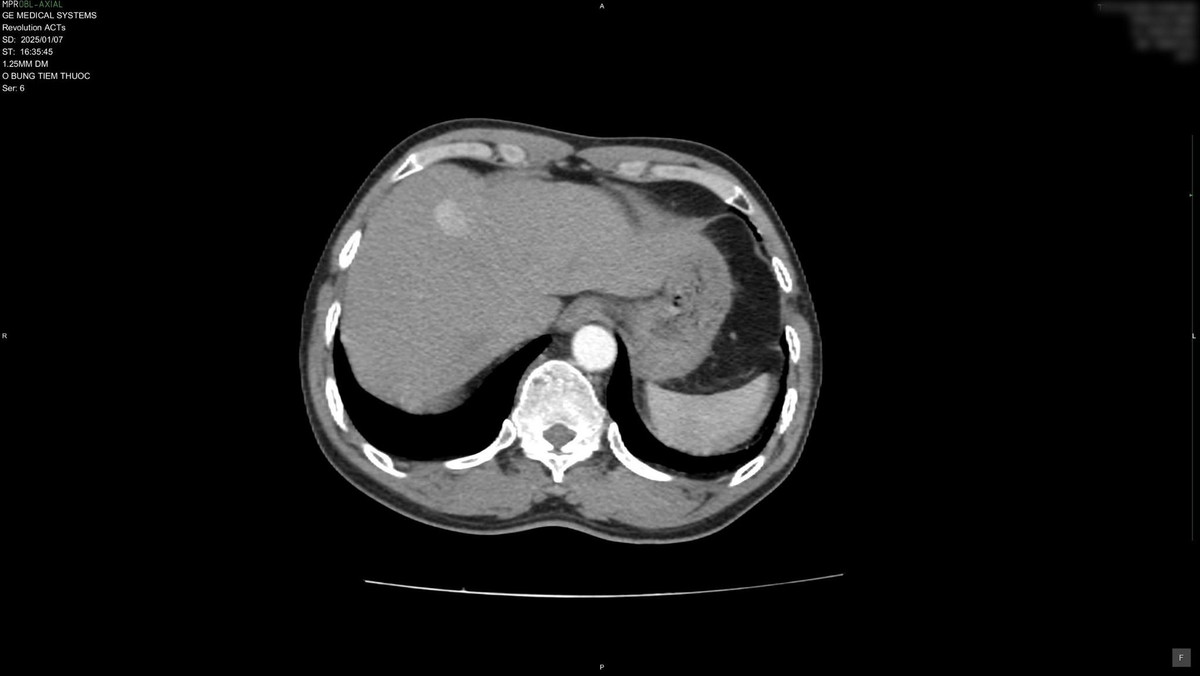

Tại đây, kết quả chụp CLVT ổ bụng có thuốc cản quang cho thấy khối u gan kích thước 22x13mm. Bệnh nhân được tư vấn lên tuyến truyền khám và điều trị chuyên sâu.

| Kết quả chụp CLVT ổ bụng có thuốc cản quang cho thấy khối u gan kích thước 22x13mm. Ảnh TTYT huyện Thanh Ba (Phú Thọ) |